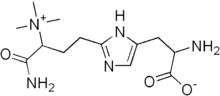

The diphtheria toxin has the same mechanism of action as the enzyme NAD(+)—diphthamide ADP-ribosyltransferase (EC 2.4.2.36). It catalyzes the ADP ribosylation of the unusual amino acid diphthamide in eEF-2 by transferring the ADP-ribosyl group from NAD+. The ADP ribosylation of diphthamide inactivates the eEF-2 protein, thus, inhibiting the translation of mRNA. The catalysed reaction is as follows:

- NAD+ + peptide diphthamide nicotinamide + peptide N-(ADP-D-ribosyl)diphthamide.

The exotoxin A of Pseudomonas aeruginosa uses a similar mechanism of action.